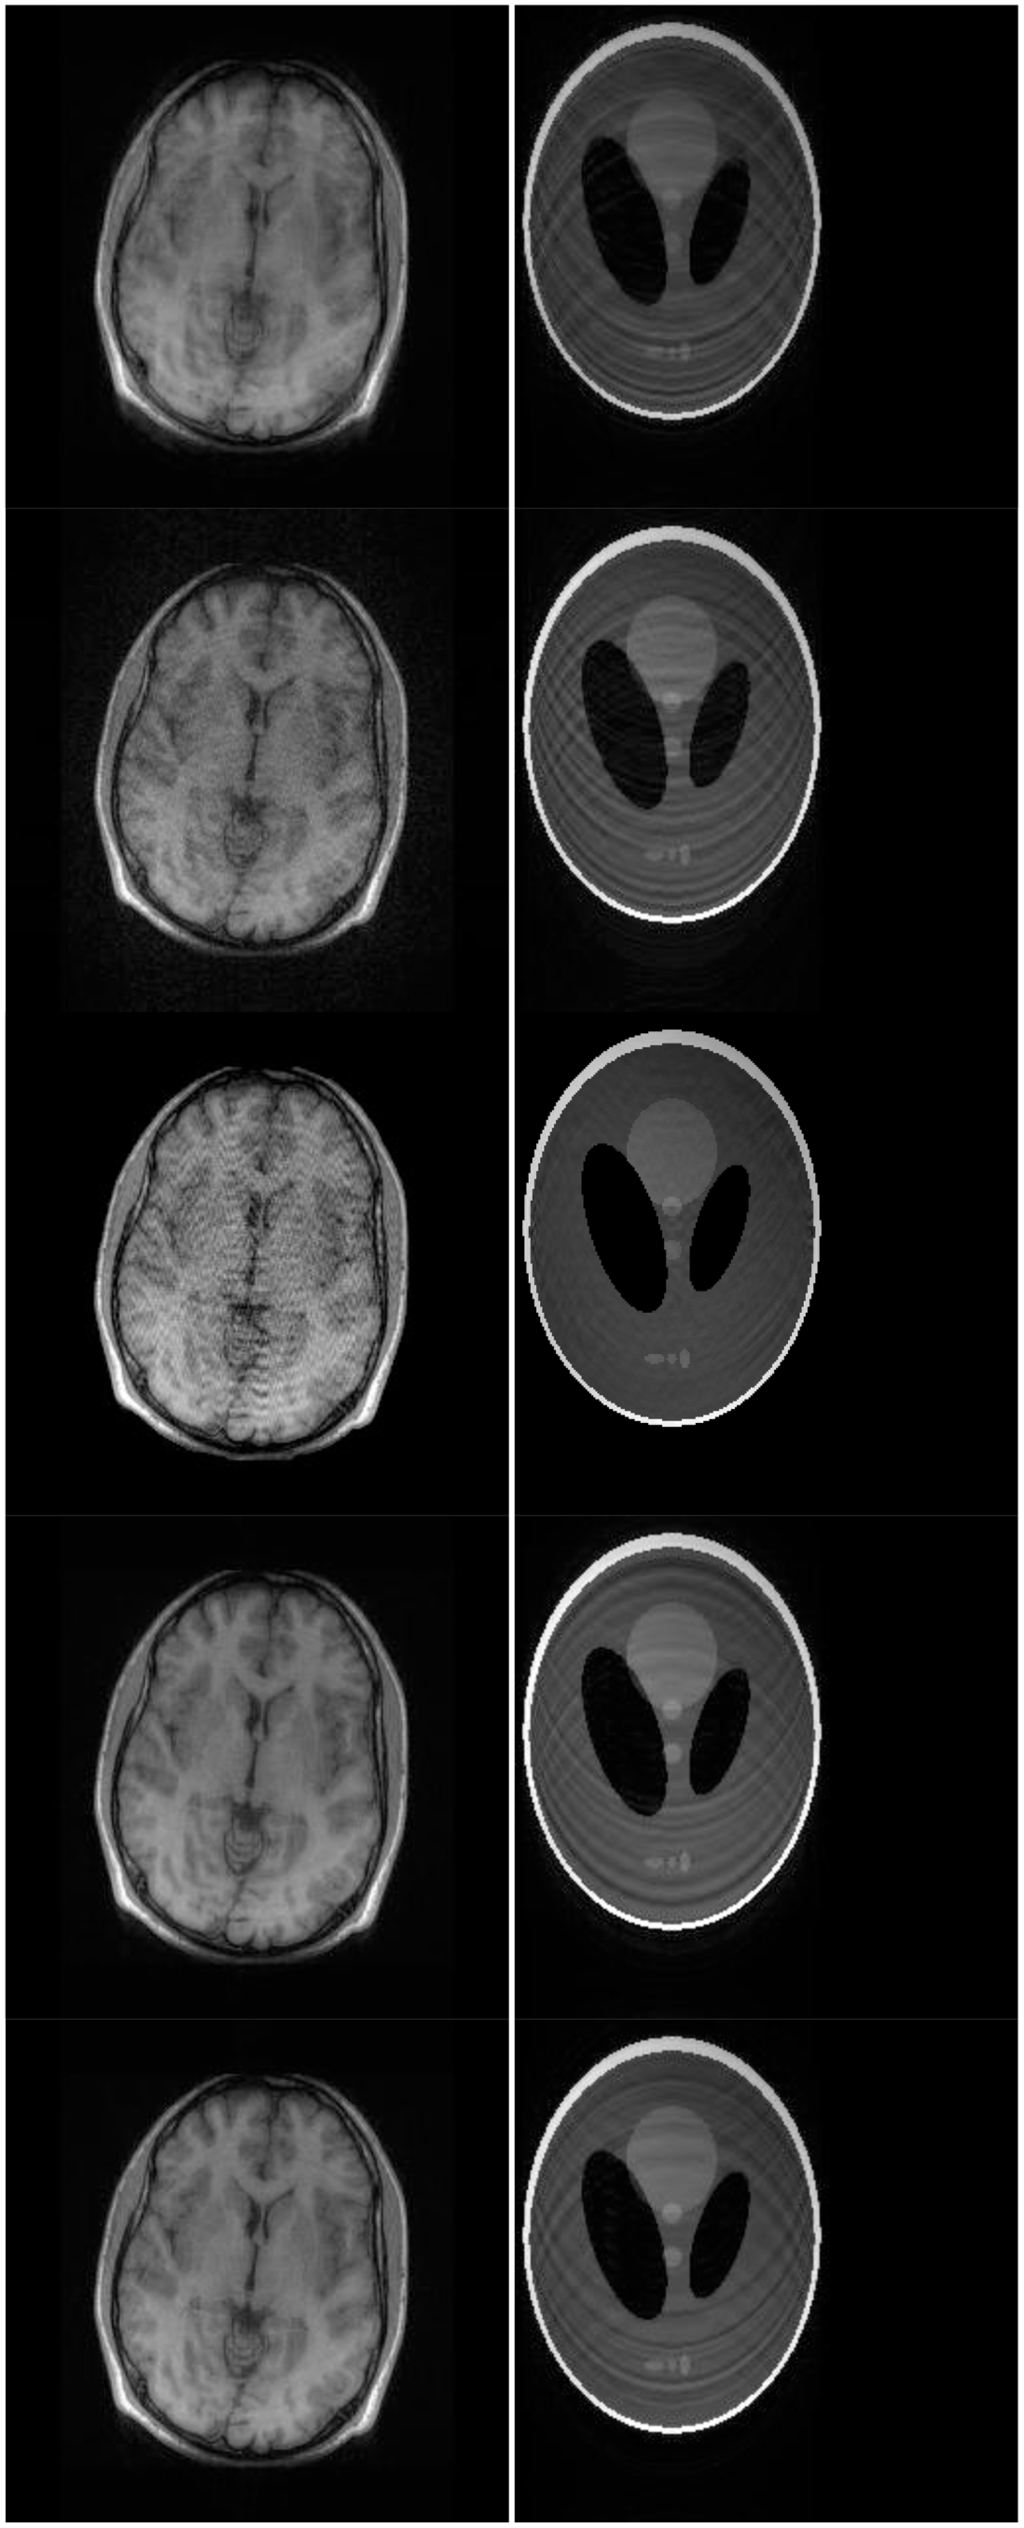

There are two sets of ground-truth data used for our experimental evaluation (Figure 7). The brain data and the Shepp-Logan phantom have been used previously in [4]. The brain data is a fully sampled T1 weighted scan of a healthy volunteer. The volunteer was scanned using Spoiled Gradient Echo sequence with the following parameters—echo time = 8 ms; repetition time = 17.6 ms; flip angle = 20 degrees. The scan was performed on a GE Sigma-Excite 1.5-T scanner, using an eight-channel receiver coil. The 8-channel data for Shepp-Logan phantom was simulated. The ground-truth is formed by sum-of-squares reconstruction of the multi-channel images.

Although NMSE is an often used metric for evaluating the reconstruction accuracy, it does not always reflect the qualitative aspects of reconstruction. For qualitative evaluation we show the reconstructed images in Figure 9. Owing to limitations in space we only show the results for variable density random sampling. The qualitative results more or less corroborate the quantitative results. With 6-fold undersampling, all the methods apart from our proposed analysis prior formulation yields significant reconstruction artifacts.

In order to elucidate the reconstruction even more, we show the difference (between groundtruth and reconstructed) images for the brain image. The difference images are shown in Figure 10. The contrast of the difference images have been enhances five times for visual clarity. The difference images corroborate our previous findings. We see that the DCS reconstruction yields the worst results. CS SENSE and SAKE yields almost similar difference images; l1SPIRiT slightly improves upon CS SENSE and SAKE. Our analysis prior formulation yields the best results; the synthesis prior is better than l1SPIRiT bust is slightly worse than the analysis prior.